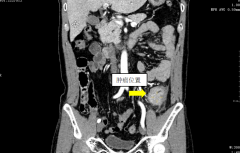

肚疼不要大意!东莞两名男士肚疼都被查出肠癌!

日常生活中,肚子疼很常见,但肚子疼,可小可大。有时是肠...